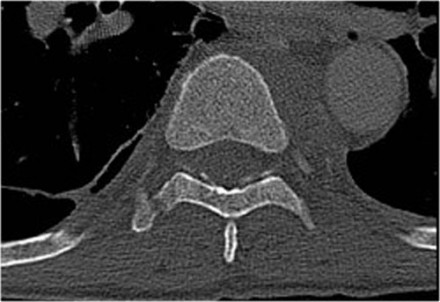

In this case of translation there is bilateral facet dislocation and also a horizontal fracture of the spinous process.

There is severe narrowing of the spinal canal.